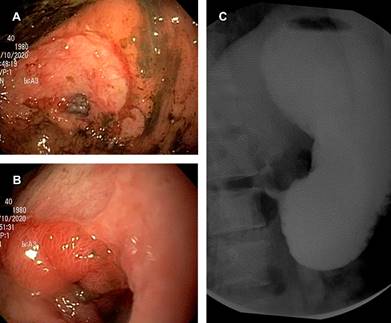

Los laboratorios mostraron anemia hipocrómica microcítica grado II y antígeno carcinoembrionario 0.96 ng/mL. Se efectuaron panendoscopias, la inicial (Figura 1A y B), a los 15 días con dilatación, a los dos meses con dilatación y a los tres meses. La inicial mostró zona de ulceración desde la incisura angularis hasta el píloro, con sangrado, sin permitir paso del panendoscopio.

Figura 1: Imágenes endoscópicas de porción antral gástrica. Se observa: en (A) zona de ulceración desde la incisura angularis hasta el píloro, con sangrado; en (B) estenosis pilórica; y en (C) sin permitir el paso del panendoscopio.

La serie esofagogastroduodenal mostró paso filiforme de contraste hacia el píloro (Figura 1C). La tomografía computarizada de tórax y abdomen reportó engrosamiento de la mucosa del antro y bulbo duodenal y ganglios de aspecto inflamatorio.